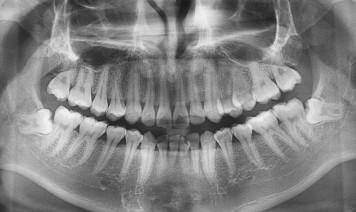

长智齿的时候,我们多少会觉得很痛。有的人忍受不了这般疼痛,想拔牙一拔了之。天津海德堡口腔专家表示,虽然智齿用处不大,然而进行拔除也不必力度过硬,因为不是所有的智齿都应该拔掉的,那么,哪些牙齿才需要拔除呢?  需要拔掉的智齿有:

第一、蛀牙,如果智齿发生蛀牙,除了很简单的咬合面不深的蛀牙可以补之外,那些邻接面蛀牙,以及蛀得很深,甚至需要根管治疗的,建议拔除,杜绝后患。

第二、还有一种就智齿阻生,现实也证明,智齿阻生是智齿拔牙最常见的类型。智齿阻生指的是:智齿长不出來,残余的牙胚有可能会变性而形成口腔肿瘤。

海德堡口腔医院专家指出,阻生齿可能成为某些原因不明疼痛的病灶,异位或萌出不全的智齿亦往往会对正常咬合造成干扰,牵动下颌骨之肌肉必须常常作出异常收缩来避开这一干扰,智齿牙痛就由此而来。